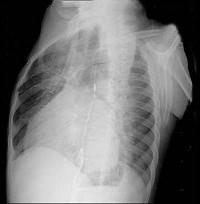

问题 56岁男性患者,劳累后心慌气促10余年,近来自觉症状加重。临床听诊,心尖区有舒张期隆隆样杂音,行胸部X检查,如图所示,你认为下列描述正确的是 ( )

选项 A、考虑三尖瓣狭窄 B、考虑二尖瓣狭窄 C、心后上缘后突压迫冲钡食管 D、左前斜位示心影向后下方突出 E、右前斜位示左心房增大

答案 BCDE